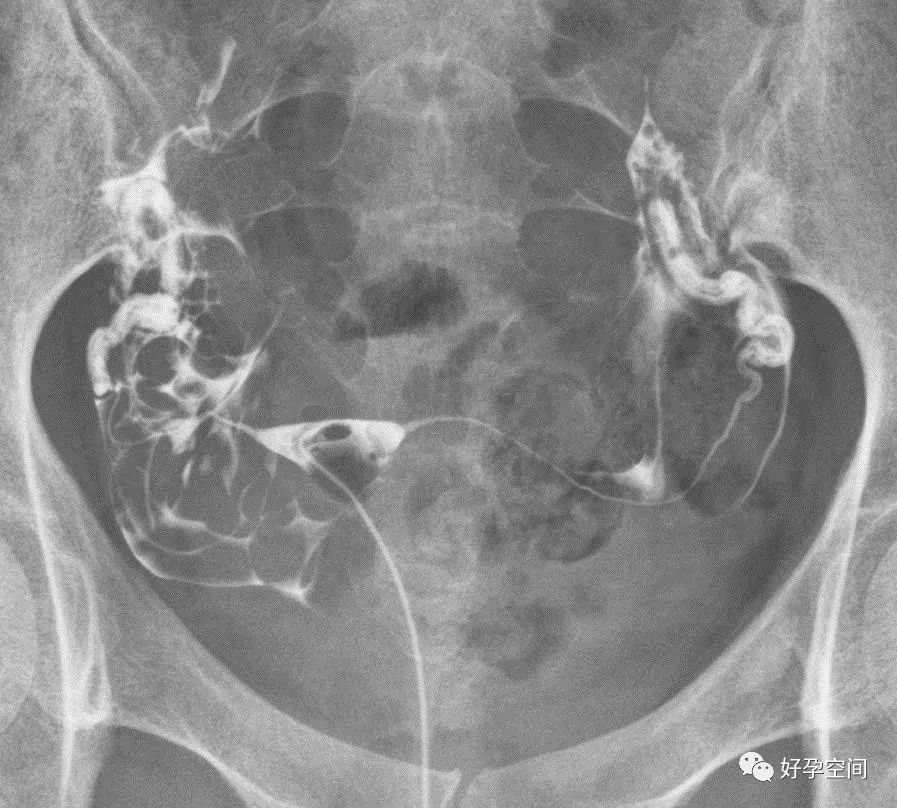

5、正常输卵管走行:正常的输卵管是从子宫角的尖端起,呈自然流线形,输卵管走行不固定,两侧输卵管不一定对称,输卵管活动度很大,走行分四型:(1)上行,和宫体连接呈缠绕状,在子宫底两侧弯弯曲曲上行,壶腹部远段和伞部向下屈曲。(2)反向走行,一侧上行,另一侧下行。(3)下行,和宫体连接呈缠绕状,在子宫两侧弯弯曲曲下行,壶腹部远段和伞部向上屈曲。(4)水平走行,在宫底水平向两侧呈伸展状。

双侧输卵管上行

双侧输卵管反向走行(一侧上行,对侧下行)

双侧输卵管下行

双侧输卵管水平走行